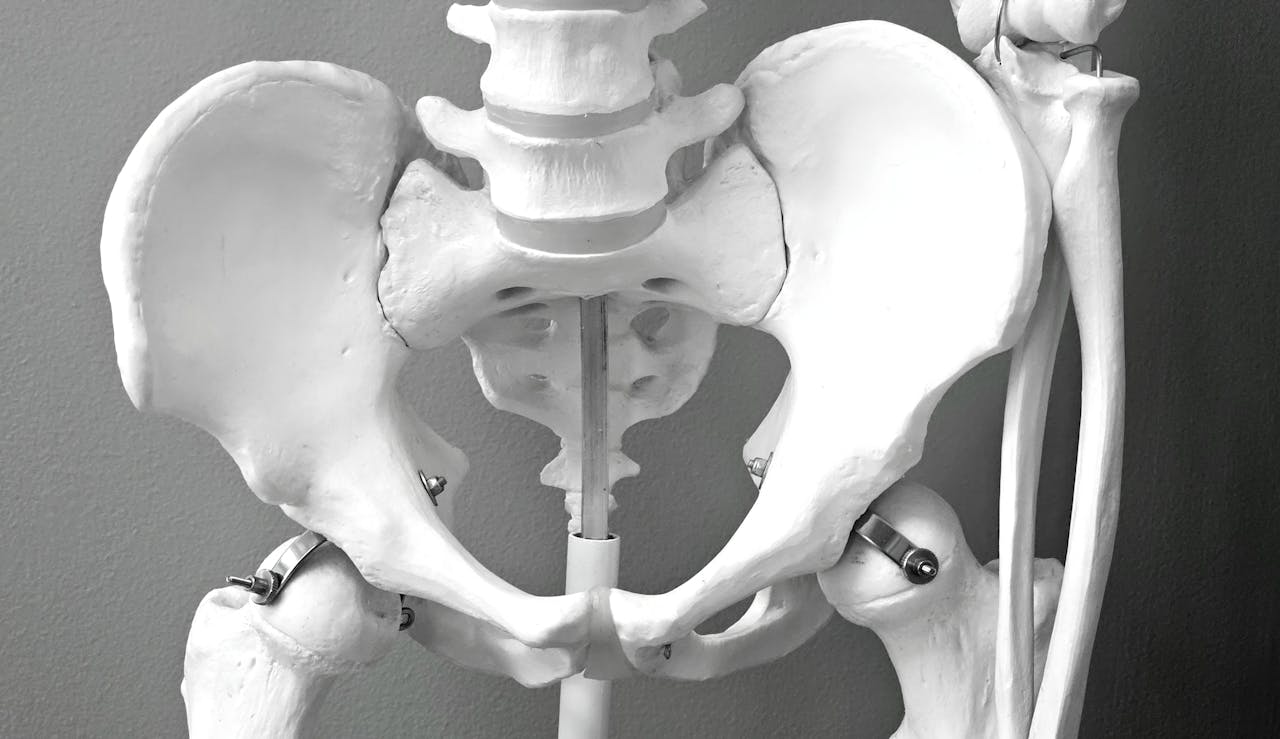

Estos músculos se sitúan en la parte inferior de la pelvis y actúan como una especie de “hamaca” que sostiene órganos como la vejiga, el intestino y, en el caso de las mujeres, el útero. Además de su función de soporte, el suelo pélvico participa en el control de esfínteres, la estabilidad del tronco y la función sexual. Cuando está fuerte y flexible, permite que estas funciones se realicen de manera eficiente; cuando se debilita o se tensa en exceso, pueden aparecer distintos problemas.

En las mujeres, la salud del suelo pélvico suele asociarse con el embarazo, el parto y la menopausia, etapas en las que estos músculos enfrentan cambios importantes. Un suelo pélvico debilitado puede contribuir a la incontinencia urinaria, al prolapso de órganos pélvicos o a molestias durante las relaciones sexuales. No obstante, estos problemas no son “normales” ni inevitables, y pueden prevenirse o tratarse con ejercicios y acompañamiento profesional.

En los hombres, el suelo pélvico cumple funciones igual de relevantes, aunque se hable menos de ello. Estos músculos participan en el control urinario y fecal, así como en la función eréctil y eyaculatoria. Alteraciones en esta zona pueden estar relacionadas con incontinencia tras cirugías de próstata, dolor pélvico crónico o dificultades sexuales. Visibilizar la importancia del suelo pélvico masculino ayuda a romper estigmas y a promover una atención preventiva.